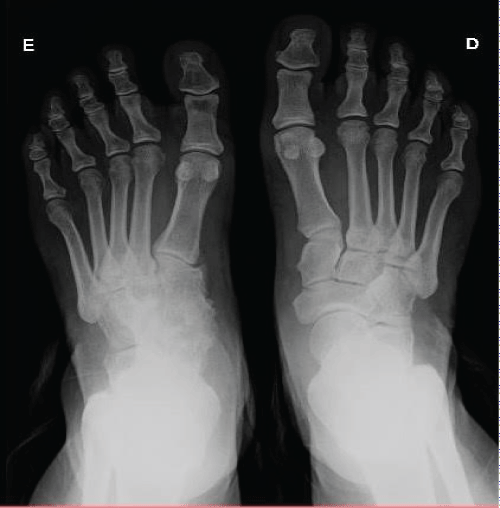

Thirteen years after the initial injury, the patient consulted again with no complaint in operated tarsus, reporting being able to dance and walk normally. Radiography and ultrasonography performed on both feet, and they demonstrated that arthrodesis consolidated on the left foot (Figure 6). The consolidation is as expected and it does not cause major movement limitation to the patient.

Figure 6: Antero-posterior plain X-ray 13 years after ORIF showing the consolidation in her left foot.